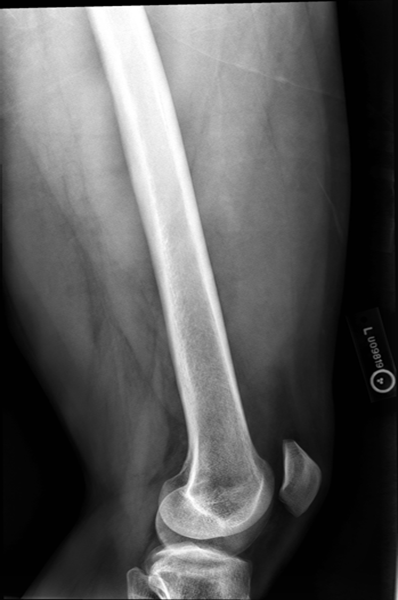

Lateral Femur

•Evidence of proper collimation and the presence of a side marker placed clear of the anatomy of interest

•Most of the femur and the joint nearest to the pathologic condition or site of injury (a second projection of the other joint is recommended)

•Any orthopedic appliance in its entirety

•Bony trabecular detail and surrounding soft tissues

With knee included (distal)

•Superimposed anterior surface of the femoral condyles

•Patella in profile

•Open patellofemoral space

•Inferior surface of the femoral condyles not superimposed because of divergent rays

Under-rotated, sticking out laterally REPEAT, place marker bottom of light field

Can not see e lesser trochanter, can not see the greater trochanter sticking out laterally, OVER ROTATED can not see lesser

Under rotated, prominent lesser trochanter, femur is not parallel, not fully lateral, wide collimation

REPEAT under rotation

Condyle is coming into patellafemoral joint space, condyle coming down and infront, ROTATION, medial condye is inferior, medial condyle is towards patella, over-rotation

fibula is popping out back

Not enough anatomy, under exposed, medial is pretty aligned, no rotation on image, increasing technique move central ray distally.